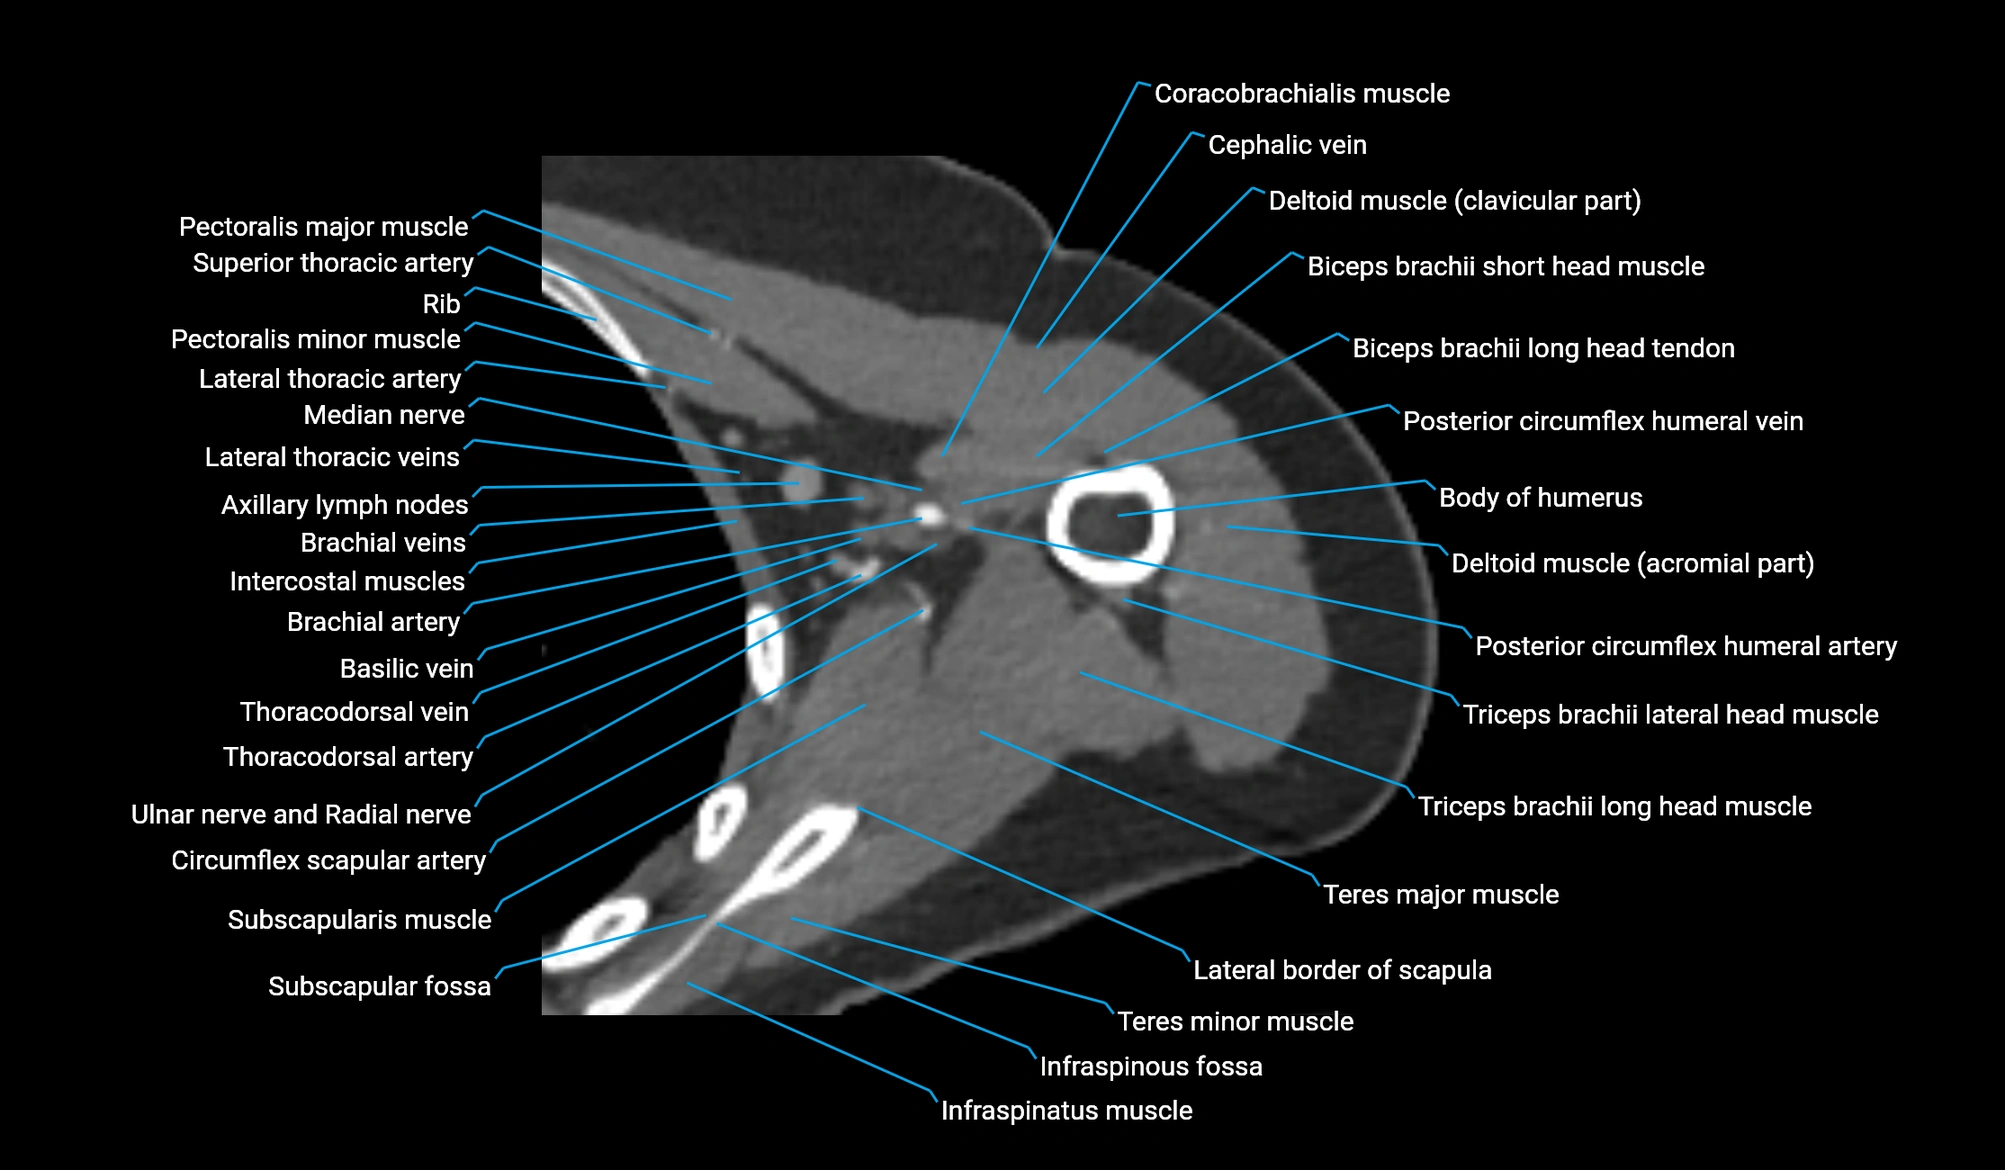

- Axillary lymph nodes

- Cephalic vein

- Circumflex scapular artery

- Clavicular part of deltoid muscle

- Coracobrachialis muscle

- Infraspinatus muscle

- Infraspinous fossa

- Lateral border of scapula

- Median nerve

- Pectoralis major muscle

- Pectoralis minor muscle

- Posterior circumflex humeral artery

- Posterior circumflex humeral vein

- Subscapular fossa

- Subscapularis muscle

- Teres major muscle

- Teres minor muscle

- Thoracodorsal artery